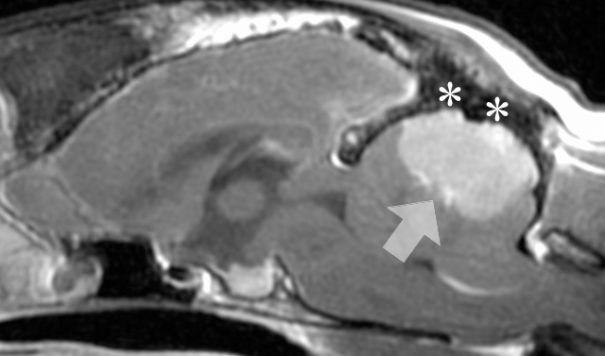

- 3D képalkotás: MRI (esetleg CT) vizsgálat, mely altatásban történik. Az MRI részletesebben leképezi az agy szerkezetét, mint a CT, ezért lehetőség szerint az MRI választandó.

A CT-képeken felderíthető a meningioma és a choroid plexus tumorok többsége, de kevésbé alkalmasak pl. a gliomák azonosítására.

A daganat szövettani típusa sokszor gyanítható a CT vagy MRI felvételeken történő megjelenése alapján, de csak akkor lehet pontosan azonosítani, ha a daganatból mintát veszünk, akár műtéti úton, vagy CT vezérelt biopsziával, erre azonban hazánkban nagyon ritkán kerül sor a beavatkozás kockázata, költsége és a komplex eszköz- és szaktudásigénye miatt. Ennek hiányában azonban gyakran nincs biztos diagnózis, csak feltételezett kórmeghatározás történik, ezért különösen fontos minden egyéb kórfolyamatot kizárni, amennyire csak lehetséges.

Megjegyzés: a képért köszönet Dr. Garamvölgyi Ritának (Kaposvári Egyetem Diagnosztikai és Onkoradiológiai Intézet)